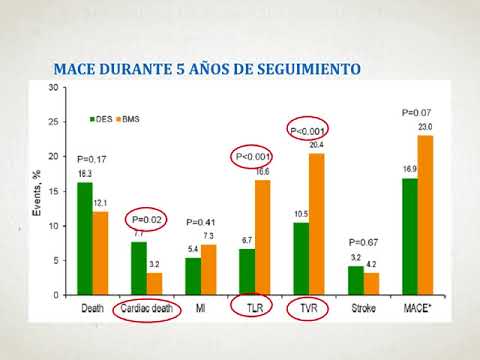

Eficacia y seguridad de los stent liberadores de droga optimizados por biocompatibilidad vs. stent metálicos con solo un mes de doble antiagregación. Dra. Florencia Cichello. Residencia de Cardiología. Hospital C. Argerich. Buenos Aires